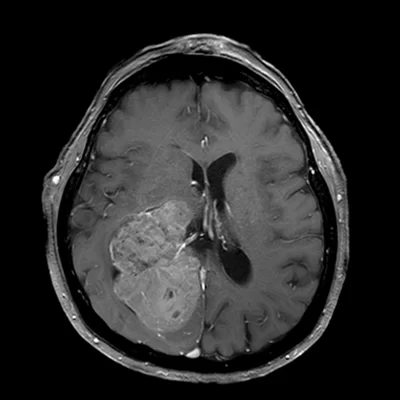

Το 90% των μηνιγγιωμάτων εμφανίζονται εντός του κρανίου, σε διάφορες θέσεις τόσο στην κυρτότητα όσο και στη βάση του κρανίου. Μερικές φορές εμφανίζονται σε σπάνιες θέσεις, όπως για παράδειγμα εντός του σπονδυλικού καναλιού, εντός των κοιλιών του εγκεφάλου (Εικόνα 1) ή στο οπτικό νεύρο.

Η διάγνωση συνήθως τίθεται με τον νευροαπεικονιστικό έλεγχο, δηλαδή με την μαγνητική και αξονική τομογραφία εγκεφάλου. Ανάλογα με την εντόπιση, ενδεχομένως να χρειαστούν πιο εξειδικευμένες εξετάσεις όπως πχ. οφθαλμολογική εκτίμηση για έναν όγκο κοντά στο οπτικό νεύρο.